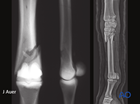

Metacarpals/-tarsals III: Proximal simple fractures

Plate fixation